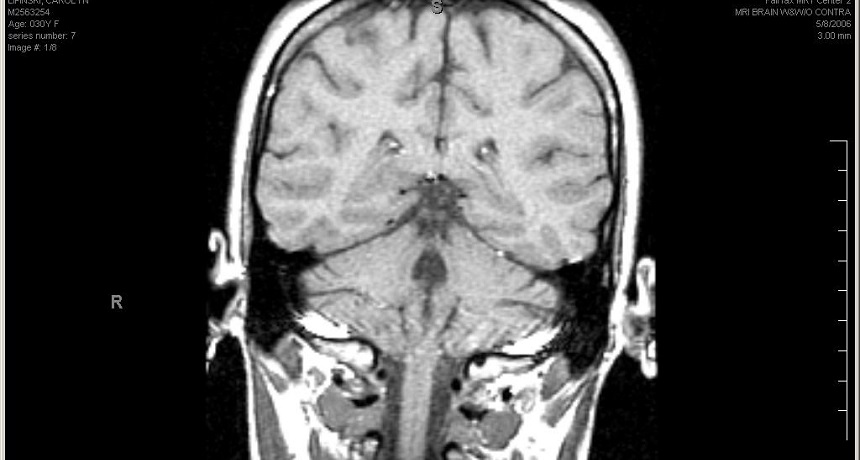

This is a magnetic resonance image of the inside of someone’s head. MRI can show the brain in beautiful detail.

Carolyn/ (CC BY-NC-SA 2.0)